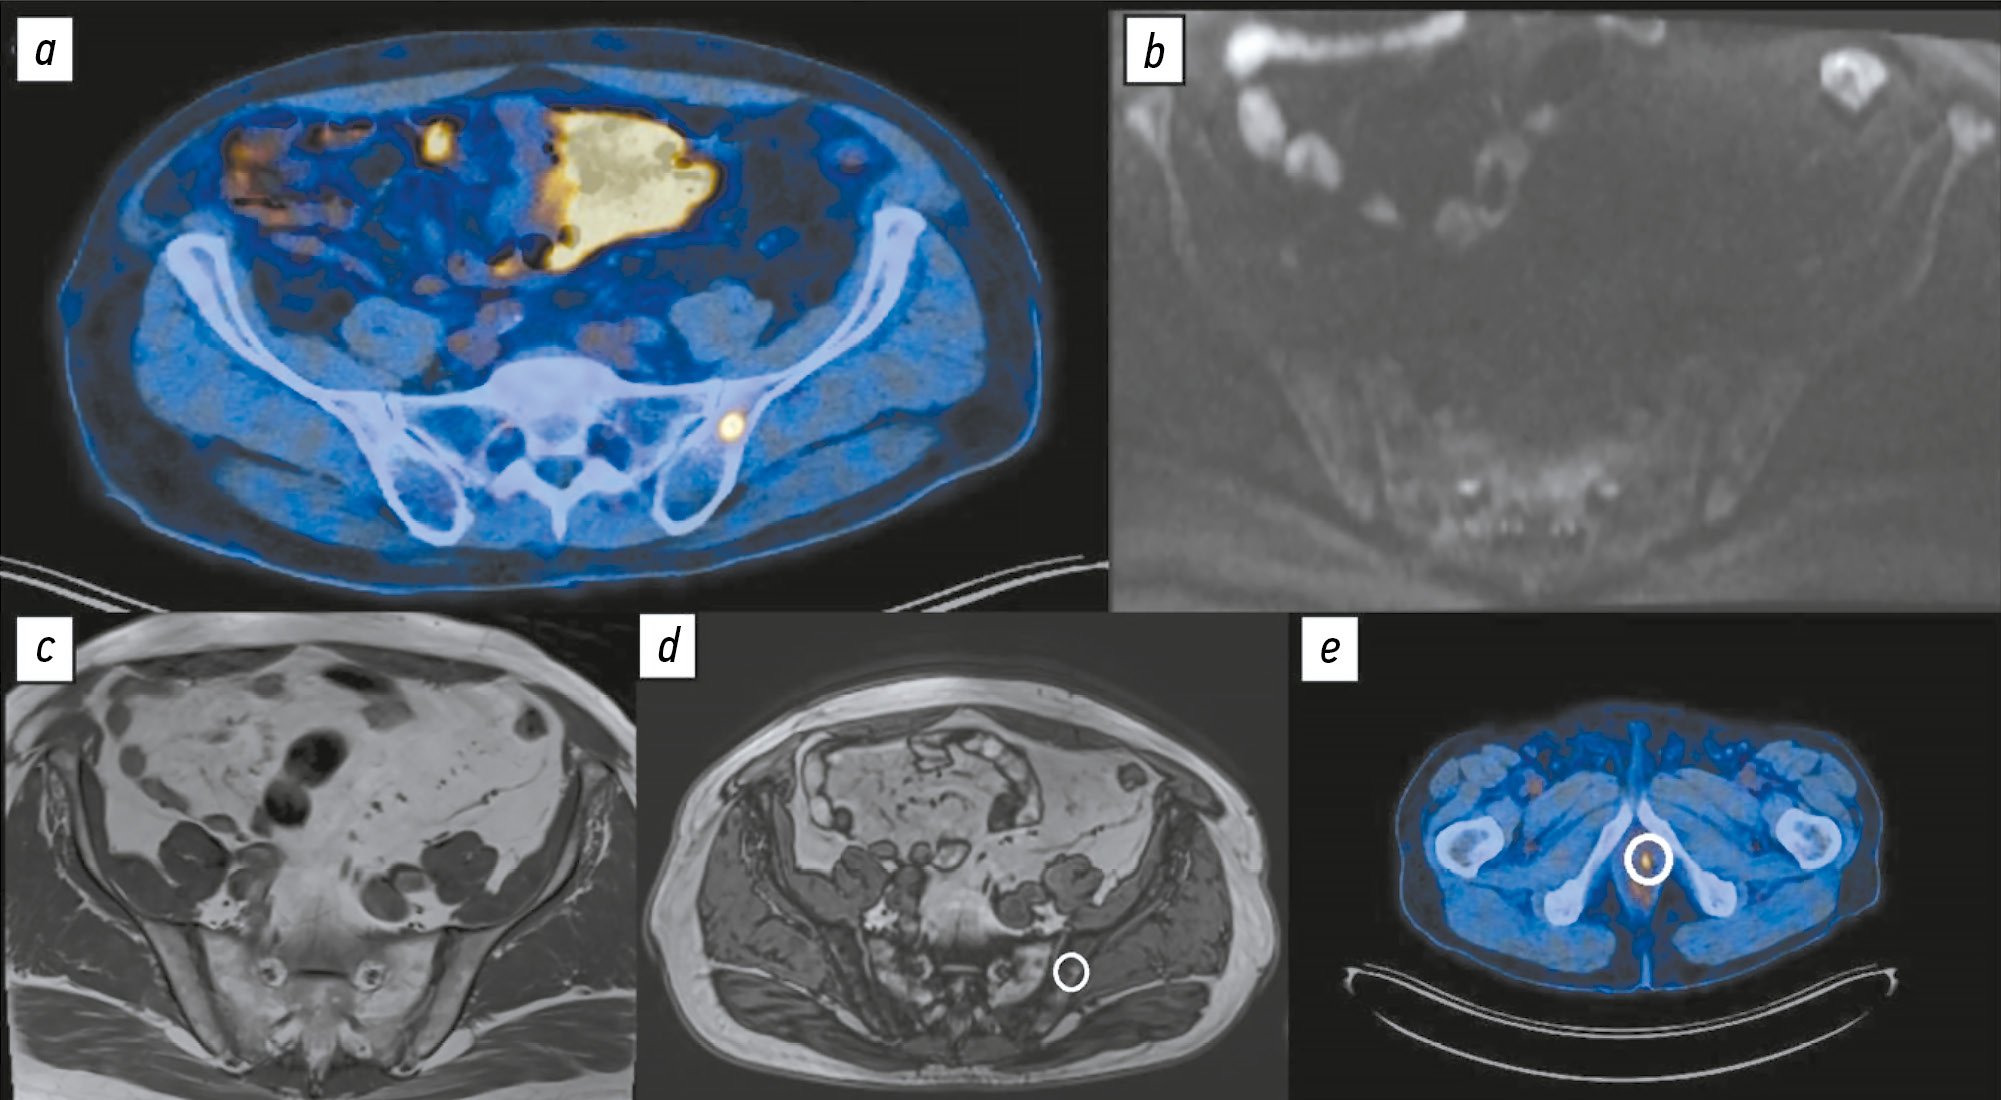

Comparison of the diagnostic accuracy of whole-body diffusion-weighted imaging and 18F-prostate-specific membrane antigen-1007 positron emission tomography combined with computed tomography for detecting bone metastases in prostate cancer

Abstract

BACKGROUND: The increasing availability of 18F-prostate-specific membrane antigen-1007 (18F-PSMA-1007) for prostate cancer staging highlighted its advantages, particularly its higher spatial resolution compared to analogs. Moreover, accumulating scientific data indicate an increase in false-positive findings, predominantly in bones, which may lead to unwarranted upstaging of the disease. Diffusion-weighted imaging may be used for the early detection of bone metastases.

AIM: This study aimed to assess and compare the diagnostic accuracy of whole-body 18F-PSMA-1007 positron emission tomography combined with computed tomography and whole-body and pelvic bone diffusion-weighted imaging in patients with prostate cancer.

METHODS: A retrospective single-center selective study was conducted. The imaging results of 119 patients with prostate cancer were divided into two groups: group 1 comprised 40 pairs of 18F-PSMA-1007 positron emission tomography combined with computed tomography and whole-body diffusion-weighted magnetic resonance imaging scans, and group 2 included 79 pairs of similar studies, with magnetic resonance imaging performed only for the pelvic bones. The diagnostic studies were performed at an inter-study interval ≤14 days. The metastatic bone lesions detected in different anatomical regions was counted using data from 18F-PSMA-1007 positron emission tomography combined with computed tomography and magnetic resonance imaging. Lesions were considered true positives if confirmed by additional magnetic resonance imaging pulse sequences and/or follow-up observation.

RESULTS: Whole-body diffusion-weighted imaging demonstrated higher specificity (58.1%) for detecting bone metastases than 18F-PSMA-1007 positron emission tomography combined with computed tomography (51.06%). However, its sensitivity was lower: 93.22% versus 97.55%.

CONCLUSION: Despite its advantages, 18F-PSMA-1007 positron emission tomography combined with computed tomography shows a high rate of false-positive bone findings. These are most commonly noted in the ribs, vertebrae, and pelvic bones. Suspicious bone lesions should be further evaluated to avoid unjustified disease upstaging. Thus, whole-body magnetic resonance imaging with diffusion-weighted sequences and selective fat signal suppression can be used.